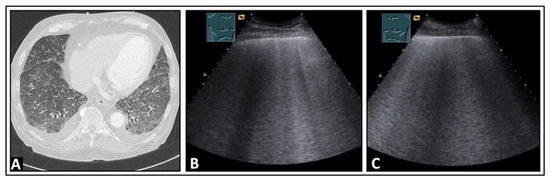

6. Interstitial Lung Disease